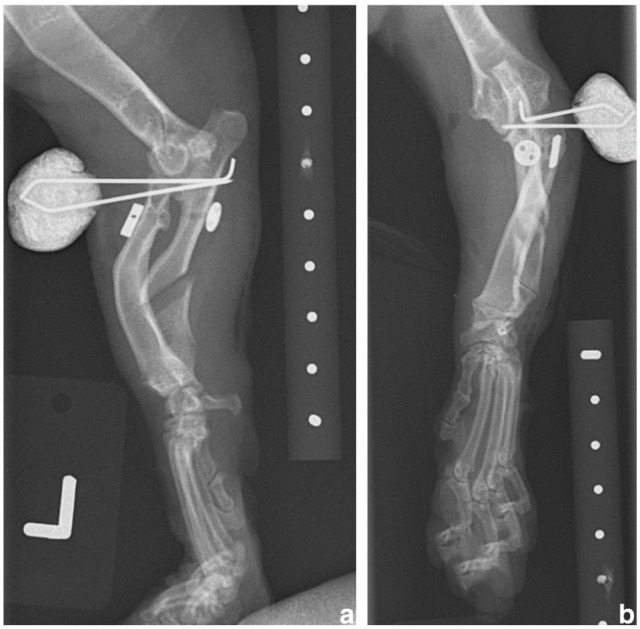

Case summary: A 10-month-old male neutered Dwelf cat with bilateral thoracic angular limb deformity secondary to chondrodystrophism presented with an acute onset of left thoracic lameness due to elbow subluxation and radial head displacement. Financial restrictions limited treatment to a single surgical procedure consisting of a left ulnar osteotomy, radioulnar polypropylene toggle placement and two temporary radioulnar transosseous K-wires. The lameness resolved but a degree of radial head subluxation persisted, radiographically similar in degree to the contralateral limb.